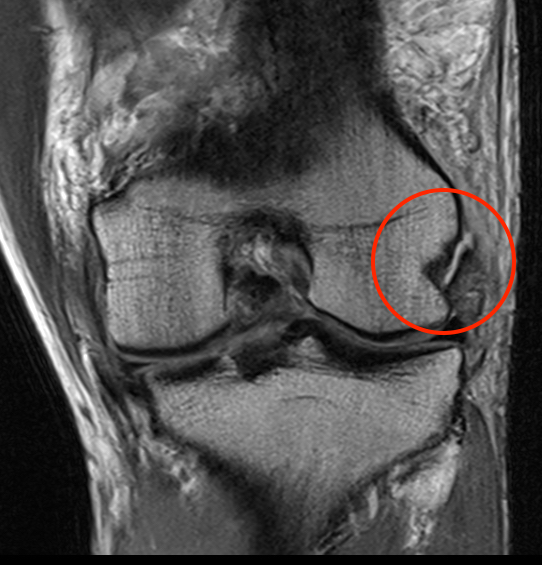

Coronal MRI of left knee demonstrating proximal MCL tear, with sagittal demonstrating complete disruption of ACL / PCL

Coronal MRI of left knee demonstrating femoral avulsion of popliteus

Coronal MRI with normal femoral insertion of LCL and popliteus

Coronal MRI of same patient demonstrating distal LCL avulsion from fibula